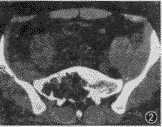

CT平扫:软组织窗(窗位51 HU,窗宽273 HU)示骶骨1~3偏右呈囊状骨质破坏,破坏区可见残存骨嵴,边界欠清楚,无明显钙化,局部轻度膨胀,范围约6.3 cm×5.2 cm,破坏区内容物CT值为21.1~51.7 HU。右髂骨内侧软组织增厚,系肿瘤突破骶骨前方骨皮质向盆腔内生长所致(图2)。骨窗示(窗位306 HU,窗宽1 494 HU):骶骨前、后方骨质破坏、缺损,并可见肿瘤组织突破骨皮质向盆腔内生长(图3)。

图2CT软组织窗示:骶骨1~3偏右有一囊状骨质破坏,破坏区可见残存骨嵴,边界欠清楚,无明显钙化,局部骶骨呈轻度膨胀,范围约6.3 cm×5.2 cm,破坏区内容物CT值为21.1~51.7 HU,右髂骨内侧软组织增厚,系肿瘤突破骶骨前方皮质向盆腔内生长